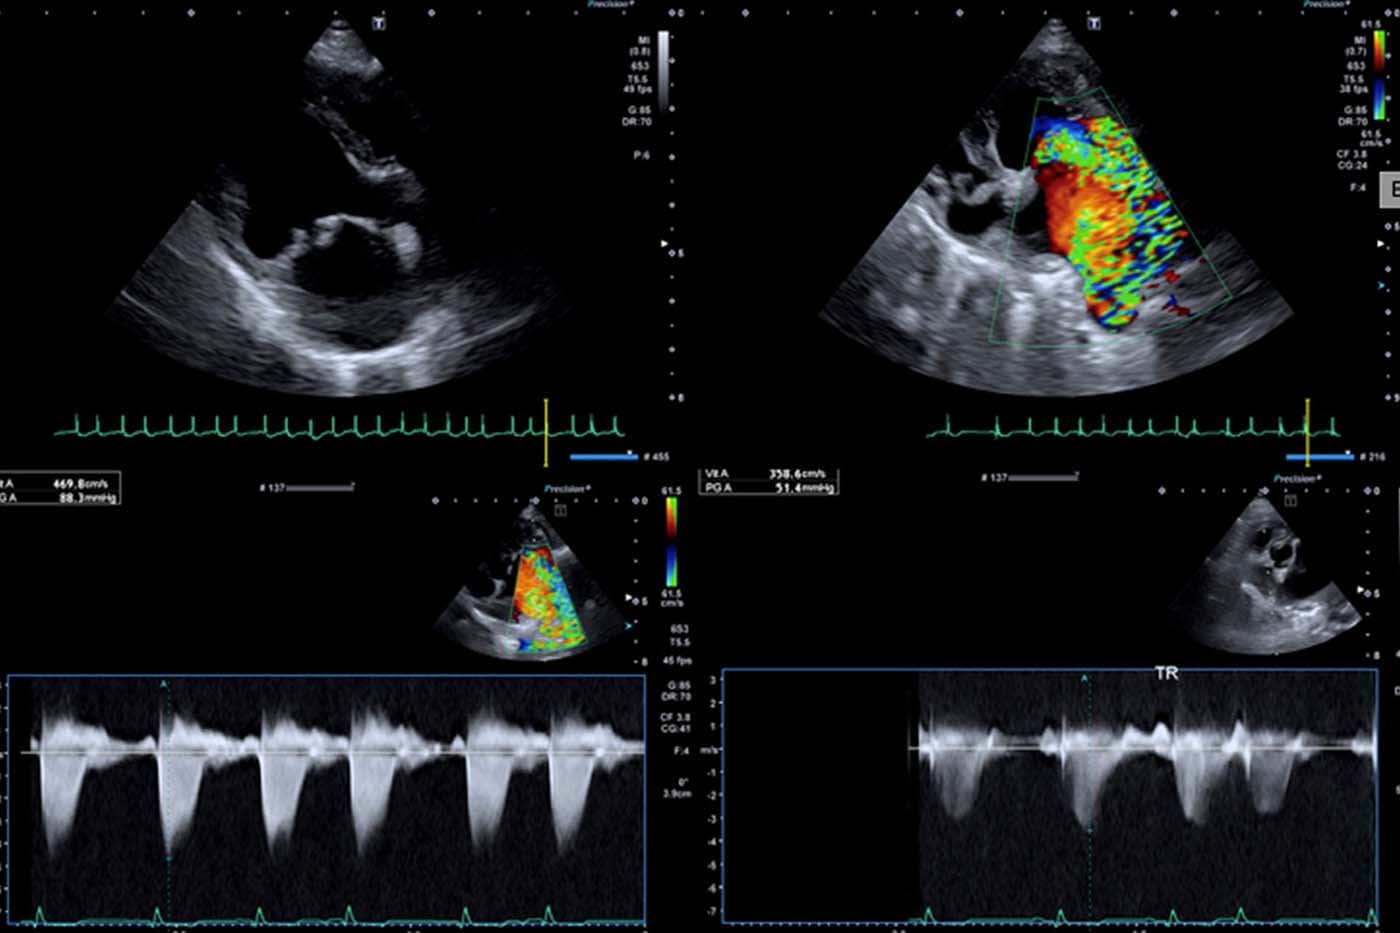

Le service de cardiologie d’AzurVet est dédié au diagnostic et à la prise en charge des affections cardiaques congénitales et acquises chez les animaux de compagnie.

Il s’appuie sur des examens spécialisés de pointe et une expertise clinique approfondie afin d’assurer un suivi précis, des traitements adaptés et une collaboration étroite avec les vétérinaires référents.

- Consultations avec échocardiographie

Ces examens permettront d’établir un diagnostic, de préciser le pronostic et de vous proposer un traitement médical (ou chirurgical si besoin).